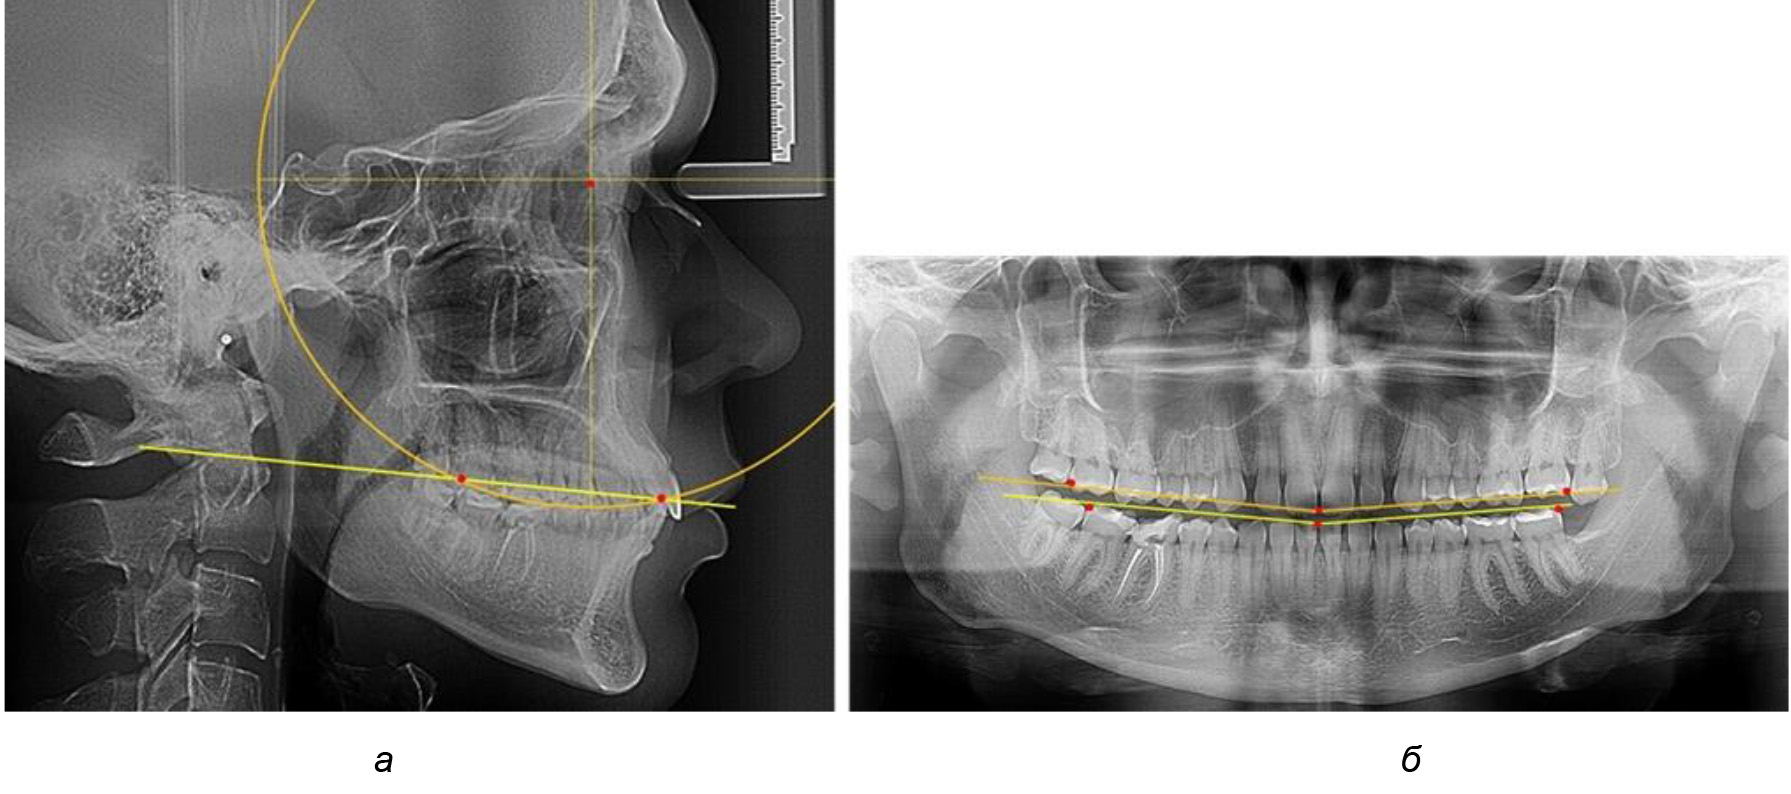

В ходе исследования установлено, что в 1-й подгруппу вошли ТРГ и ОПТГ 18 человек 1-й группы, что составило (29,03 ± 5,78) % от всех пациентов, рентгенограммы которых были проанализированы. У всех пациентов величина угла нижней челюсти была более 125° и в среднем составила (129,89 ± 3,62)° и характеризовала вертикальный тип нижней челюсти.

Учитывая существенную вариабельность линейных показателей, обусловленных типологическими (гнатическими и дентальными) вариантами зубочелюстных дуг, анализ проводили только при измерении глубины кривой Spee в наиболее углубленном месте и оценивали относительный показатель через отношение радиуса круга к сагиттальному расстоянию окклюзионной линии.

Анализ результатов показал, что глубина кривой Spee в среднем по подгруппе составил (4,12 ± 0,53) мм как при анализе ТРГ, так и ОПТГ.

Деление величины радиуса круга к длине окклюзионной линии составило 1,623 ± 0,02. Таким образом, для определения радиуса окружности, соответствующей кривизне окклюзионного контура боковой ТРГ, необходимо измерить расстояние между передней и задней окклюзионными точками и последующим умножением полученной величины на число Фибоначчи (рис. 2).

Рис. 2. Особенности кривой Spee на ТРГ (а) и ОПТГ (б) у людей с признаками вертикального роста